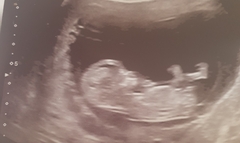

Had the scan ladies and its growing nicely such a huge difference between my 9 week and 12 week scan. Baby was moving around as well saw it kicking and wriggling I did shed a few tears as it was amazing. EDD has changed to the 4th so its moved forward a few days.

Hope your all okay look forward to seeing your scan pics.